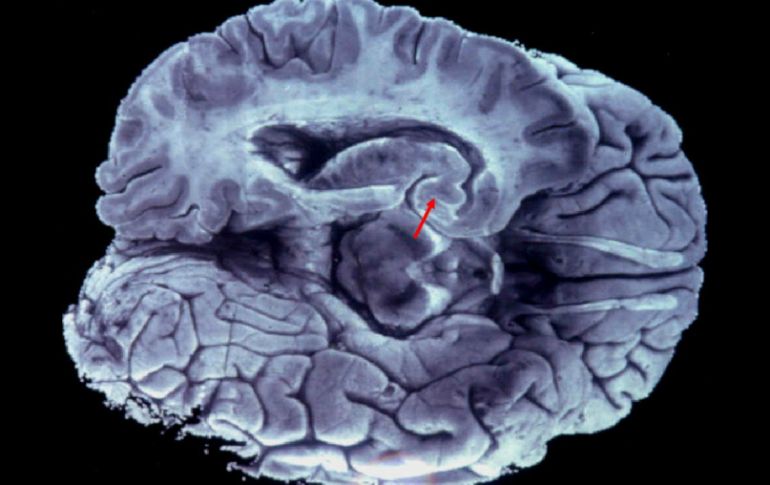

Tecnología | Estudio valida las ''experiencias cercanas a la muerte'' El cerebro agonizante exhibe actividad típica de la percepción consciente Científicos de la Universidad de Michigan demuestran que el cerebro muestra actividad conciente después de un ataque cardíaco Por: EFE 12 de agosto de 2013 - 19:01 hs El cerebro aún guarda muchos secretos, así lo han demostrado estudios recientes. ARCHIVO / WASHINGTON, ESTADOS UNIDOS (12/AGO/2013).- El cerebro agonizante de ratas de laboratorio exhibe actividades características de la percepción consciente, en un estudio que aparentemente valida las "experiencias cercanas a la muerte" de la que hablan los sobrevivientes de fallo cardíaco, según un estudio hoy en Proceedings of the National Academy of Sciences. Se ha debatido vigorosamente si el cerebro agonizante es capaz de generar actividad de conciencia y cómo lo hace. Un estudio de la Universidad de Michigan (UM) muestra que poco después de la muerte clínica, que ocurre cuando el corazón deja de latir y la sangre deja de fluir al cerebro, las ratas exhiben patrones de actividad cerebral característicos de la percepción consciente. "Este estudio, llevado a cabo en animales, es el primero que enfoca qué ocurre en el estado neurofisiológico del cerebro agonizante", indicó la autora principal del estudio, Jimo Borjigin, profesora asociada de fisiología molecular e integrativa y de neurología en la Escuela de Medicina de la Universidad de Michigan. "Esta investigación formará los cimientos de futuros estudios con humanos que investiguen las experiencias mentales que ocurren en el cerebro cuando está muriendo, incluida la visión de luz durante el arresto cardiaco", añadió. Aproximadamente, el veinte por ciento de los sobrevivientes de un paro cardiaco dan cuenta de haber tenido una experiencia cercana a la muerte durante la muerte clínica. Estas visiones y percepciones se han descrito como "más reales que la realidad", según otros estudios previos, pero todavía no se ha determinado si el cerebro es capaz de tal actividad después de un paro cardiaco. Borjigin y sus colaboradoras especularon que si la experiencia cercana a la muerte procede de la actividad cerebral, debería ser posible identificar las correlaciones neurales de la conciencia en humanos o animales aún después que cesa el flujo sanguíneo al cerebro. Las investigadoras analizaron los registros de actividad cerebral llamados electroencefalogramas de nueve ratas anestesiadas que transcurrían un paro cardiaco inducido experimentalmente. Dentro de los primeros treinta segundos después del arresto cardiaco todas las ratas exhibían un incremento generalizado y transitorio de actividad altamente sincronizada que tenía todas las características asociadas con un cerebro muy excitado. Además los autores observaron patrones casi idénticos en los cerebros agonizantes de ratas que estaban siendo asfixiadas. "Los datos confirmaron nuestro pronóstico de que encontraríamos algunas señales de actividad consciente en el cerebro durante el paro cardiaco", escribió Borjigin. "Pero nos sorprendieron los elevados niveles de actividad", añadió el autor senior del estudio, el anestesiólogo George Mashour, profesor asistente de anestesiología y neurocirugía en la UM. "De hecho, en la cercanía de la muerte muchas señales eléctricas conocidas de la consciencia excedieron los niveles encontrados en el estado de vigilia, lo cual indica que el cerebro es capaz de una actividad eléctrica bien organizada durante la etapa inicial de la muerte clínica", explicó Mashour. "Este estudio nos señala que la reducción de oxígeno, o de oxígeno y glucosa durante el arresto cardiaco puede estimular una actividad cerebral que es característica del procesamiento consciente", dijo Borjigin. "También proporciona el primer marco científico para las experiencias cercanas a la muerte de las que dan cuenta muchos sobrevivientes de un paro cardiaco". Temas Ciencia médica Cerebro Lee También ¿Cómo se forman los recuerdos en la mente? Julieta Fierro será homenajeada en la FIL INAPAM: ¿Cómo solicitar un turno para consulta médica gratuita? Nobel de Química premia el desarrollo de estructuras metal-orgánicas Recibe las últimas noticias en tu e-mail Todo lo que necesitas saber para comenzar tu día Registrarse implica aceptar los Términos y Condiciones